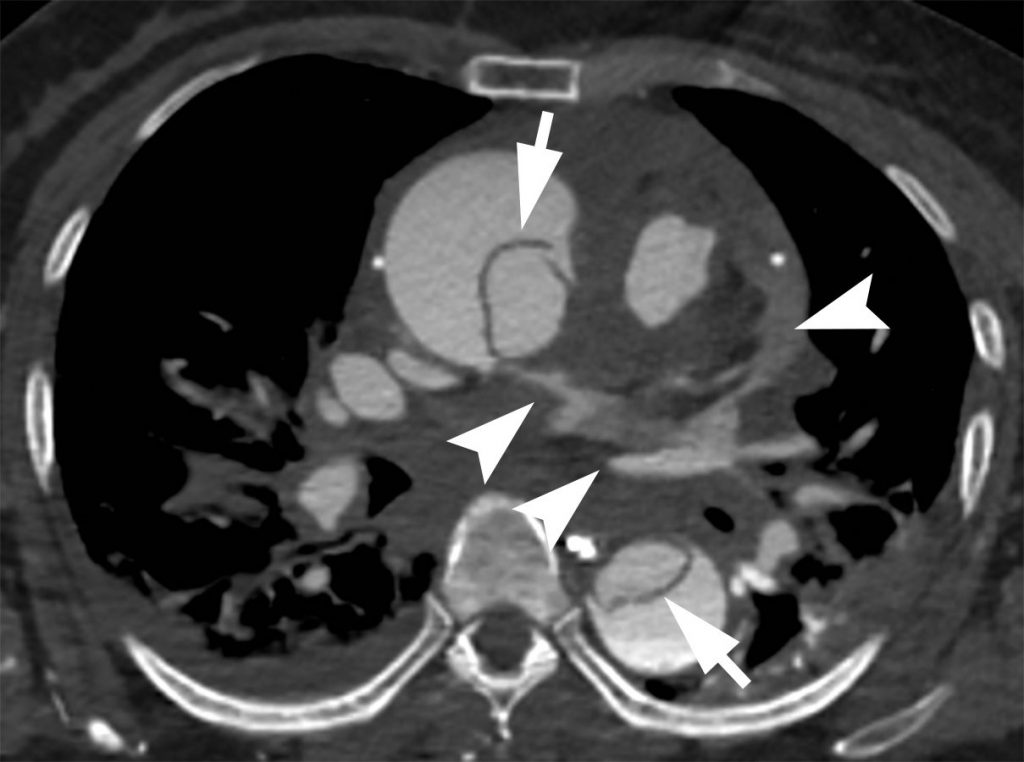

La dissection apparaît, en échographie ou sur les coupes tomodensitométriques transversales injectées et les reconstructions sagittales, sous la forme d’un flap intimal qui divise l’artère en deux chenaux :

- le vrai chenal, qui communique avec la lumière aortique depuis le ventricule gauche ;

- le faux chenal, qui prend naissance sur l’aorte ascendante ou horizontale dans le type A (figure 36.7) et après la naissance de l’artère subclavière gauche dans le type B (figure 36.8). Il peut circuler plus lentement, voire se thromboser (responsable d’un hématome pariétal), comprimer ou pas le vrai chenal, ou subir dans le temps une évolution anévrismale.

Fig. 36.7. Angioscanner thoracique en coupe axiale d’un anévrisme de l’aorte ascendante associée à une dissection de type A avec un flap intimal (tête de flèche) dans l’aorte ascendante et dans l’aorte descendante, séparant le vrai (flèche) et le faux chenal (étoile).